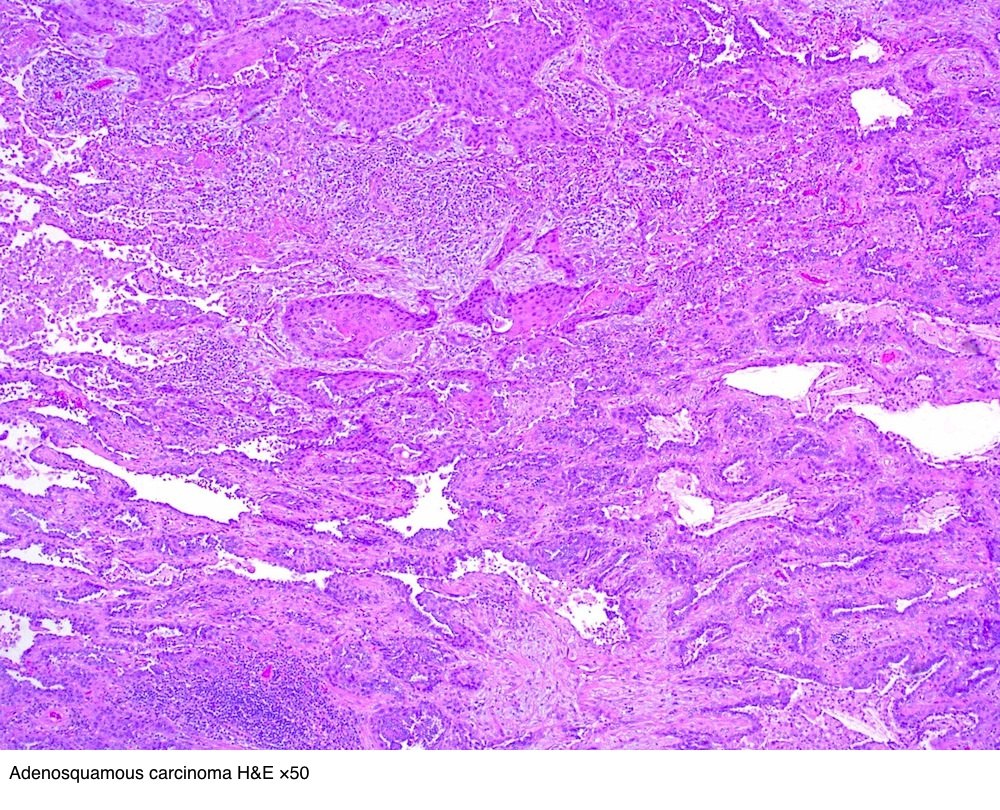

世界卫生组织who定肺腺鳞癌定义为由腺癌和鳞癌组成,且腺癌和鳞癌的组